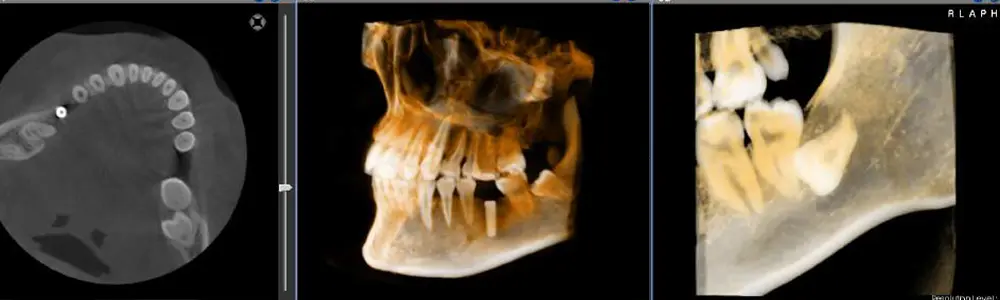

「なぜその治療が必要なのか」を明確にするために、当院では歯科用CTと、矯正専用のセファロレントゲンを活用しています。

セファロはお顔の骨格をmm単位で測定できる特殊な撮影装置です。顎の形や歯の傾き、お口のバランスを正確に知ることで、単に歯を並べるだけでなく、将来を見据えた無理のない治療計画を立てることが可能になります。目に見えない骨の状態までしっかりと把握した上で治療を進めます。